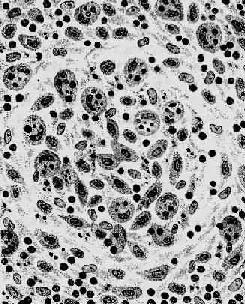

伤寒杆菌引起的炎症属急性增生性炎症,主要是巨噬细胞的增生。其吞噬能力十分活跃,胞浆中常吞噬有伤寒杆菌、受损的淋巴细胞、红细胞及坏死细胞碎屑,在病理诊断上具有一定的意义,故常称这种细胞为伤寒细胞。伤寒细胞常聚集成团,形成小结节,称为伤寒肉芽肿或伤寒小结(图18-19)。革兰染色可见伤寒细胞胞浆内含有被吞噬的伤寒杆菌。伤寒杆菌引起的炎性反应的特点是病灶内无中性粒细胞渗出。

图18-19 伤寒肉芽肿模式图

图示伤寒小结内大量增生的伤寒细胞,胞浆内含有红细胞及组织碎屑等